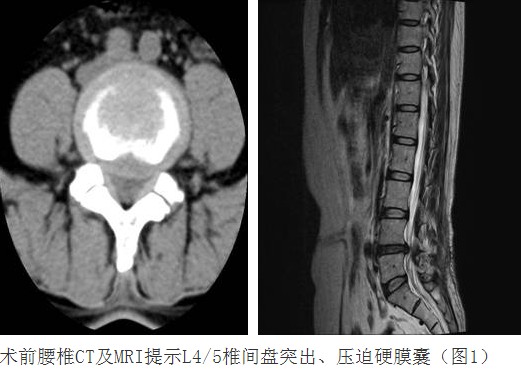

病例匯報1老年女性患者,因“反復(fù)腰腿痛10年、加重伴左下肢麻痛2月”之主訴入院,術(shù)前左下肢肌力3+級,淺感覺減退。術(shù)后腰腿疼緩解,肌力及感覺恢復(fù)正常。(1、圖2)

術(shù)后腰椎X線提示單側(cè)釘棒系統(tǒng)固定穩(wěn)妥,椎間隙高度恢復(fù)正常,融合良好。(圖2